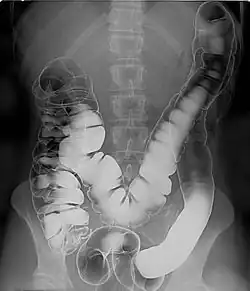

Das konventionelle Röntgen des Bauches bietet eine schnelle Diagnostik. Es eignet sich zur Identifizierung freier Luft im Bauchraum, die einen Hinweis auf die Perforation eines Hohlorgans gibt, zur Diagnostik eines Darmverschlusses (Ileus) durch den Nachweis von Luft-Flüssigkeits-Spiegeln in den Darmschlingen oder dem Nachweis von Fremdkörpern oder eingebrachten Materialien.[57] Die Computertomographie erlaubt die Beurteilung der Wandschichten des Dickdarms sowie anderer Organe und Lymphknoten, weshalb dieses Verfahren für die Stadienbestimmung von Tumoren (Staging) verwendet wird. Bei jungen Patienten mit chronisch-entzündlichen Darmerkrankungen kommt wegen der fehlenden Strahlenbelastung die Magnetresonanztomographie (MRT) zum Einsatz. Daneben spielt dieses Verfahren auch für das Staging von Rektumkarzinomen eine Rolle.[58] Kontrastmitteluntersuchungen haben wegen der Verbreitung endoskopischer Verfahren an Bedeutung verloren. Sie kommen zum Einsatz, wenn eine endoskopische Untersuchung nicht möglich ist, etwa durch eine hochgradige Stenose des Darmlumens. Mit dieser Technik können beispielsweise Divertikel dargestellt werden.[59] Die funktionelle Untersuchung des Vorgangs der Stuhlausscheidung mit Kontrastmittel oder MRT wird Defäkographie genannt.